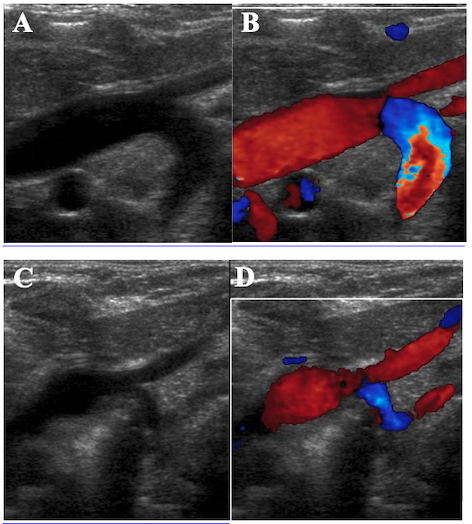

Neonato a termine nato a 38 + 0 settimane di età gestazionale, AGA (peso alla nascita 3.020 g), da gravidanza complicata da diabete gestazionale, con buon adattamento alla vita extrauterina (Apgar 8 e 9 al primo e quinto minuto rispettivamente), presenta a circa 4 settimane di vita comparsa di stridor inspiratorio associato a lieve distress respiratorio. All’obiettività clinica emergevano lievi rientramenti intercostali e al giugulo e cornage, esacerbati in pianto o in concomitanza dei pasti. La persistenza del quadro clinico ha motivato l’approfondimento diagnostico mediante videolaringotracheobroncoscopia con strumento flessibile in narcosi, che ha evidenziato compressione postero-anteriore della trachea a livello medio-distale, suggestiva per anomalia vascolare. È stata quindi eseguita un’ecocardiografia che ha posto il forte sospetto di dopio arco aortico (Figura). Tale reperto è stato quindi confermato dalla TC cuore con e senza mezzo di contrasto che documentava doppio arco aortico con ramo destro dominante e ramo sinistro ipoplasico, con compressione tracheale significativa (calibro minimo 1,5 mm) per un tratto di 5 mm. In base ai riscontri, veniva posta indicazione a correzione cardiochirurgica.

Il doppio arco aortico è una patologia rara con una prevalenza stimata di 1:15.000 nati vivi (0,05 - 0,07%), tuttavia rappresenta la più comune causa di anomalie vascolari congenite del mediastino (33 - 75% di tutti gli anelli vascolari). Tale condizione è dovuta alla persistenza del IV arco branchiale durante lo sviluppo embrionario e al fallimento della regressione dell’arco aortico destro, con formazione di due archi che circondano trachea ed esofago, generando un anello completo1,2. Nel 70 - 80% dei casi il ramo destro è dominante e il sinistro ipoplasico/atresico. La sintomatologia respiratoria precoce (stridore inspiratorio, tirage, distress durante l’alimentazione) è dovuta alla compressione tracheale e talvolta si associa anche a disfagia e difficoltà di suzione3. L’ecocardiografia è l’esame diagnostico di primo livello; è tuttavia necessario l’utilizzo della TC cardiaca per conferma diagnostica, che permette di definire morfologia, dominanza e grado di compressione tracheoesofagea ed è utile per il planning preoperatorio.